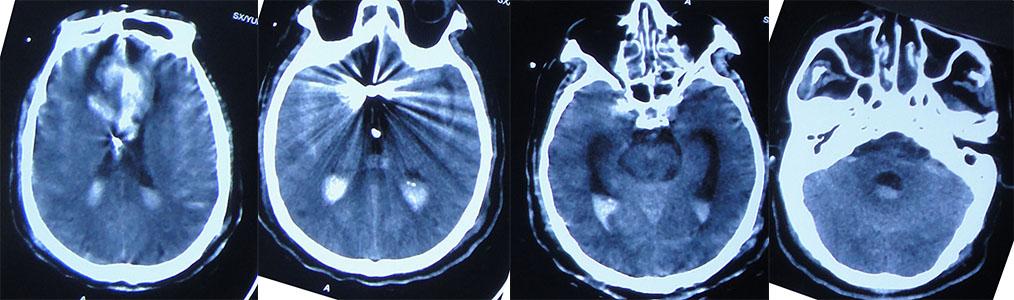

2020年10月30日-2020年11月7日,一周期间共复查4次头部CT,颅内血肿逐渐吸收,但脑室略有增大( 图-7、图-8、图-9、图-10 )。

图-7: 2020年10月30日头部CT

图-8: 2020年11月1日头部CT

图-9: 2020年11月3日头部CT

图-10: 2020年11月7日头部CT